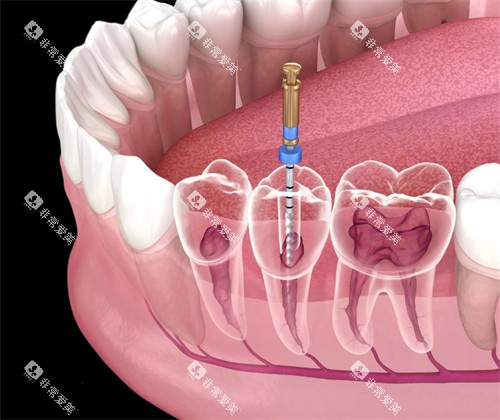

前牙根管治疗:约500元起/颗,也有480元至3000元起的说法。

后牙根管治疗:800元至2000元不等,具体价格取决于牙齿病变程度和治疗难度。

单根管治疗:390元至690元左右/颗。

双根管治疗:890元至1290元左右/颗。

多根管治疗:1900元至3900元左右/颗。

显微根管治疗:约1590元起/颗。